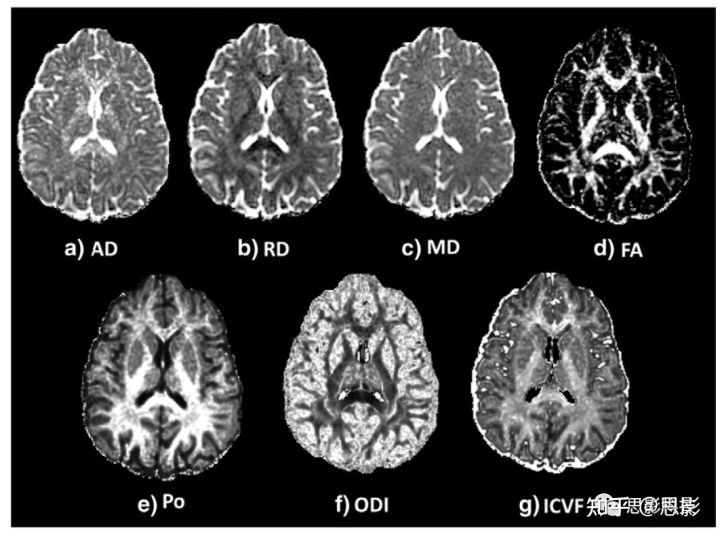

被试的AD,RD,MD,FA,P0,ODI、ICVF maps如图2所示。AD和RD仅在已知单纤维束的致密纤维束(如胼胝体和内囊)有高白质对比度。FA maps显示白质高强度,表明组织一致性高,而灰质和脑脊液低强度,表明各向同性扩散更多(图2(d))。同样,在ODI maps中,白质的强度较低(图2(e)),表明弥散度较低(即高相干性)。正如所料, P0 maps(图2(h))显示,在更受限的区域(即白质)强度更高。在ICVF maps中,白质也比灰质有更高的强度(图2(f)),这表示轴突内体积分数更高。

图2 从DTI得到轴向扩散率(AD)、径向扩散率(RD)、平均扩散率(MD)和各向异性分数(FA的图,从q-space方法得到组织限制指数(P0),从NODDI模型得到方向扩散指数(ODI)和细胞内体积分数(ICVF)的图。

AD、RD、MD的灰度值分别为0 ~1.7、1.1、1.3 × 10−3 mm2/s。FA图从0.2缩放到1。P0、ODI和ICVF映射从0缩放到1。